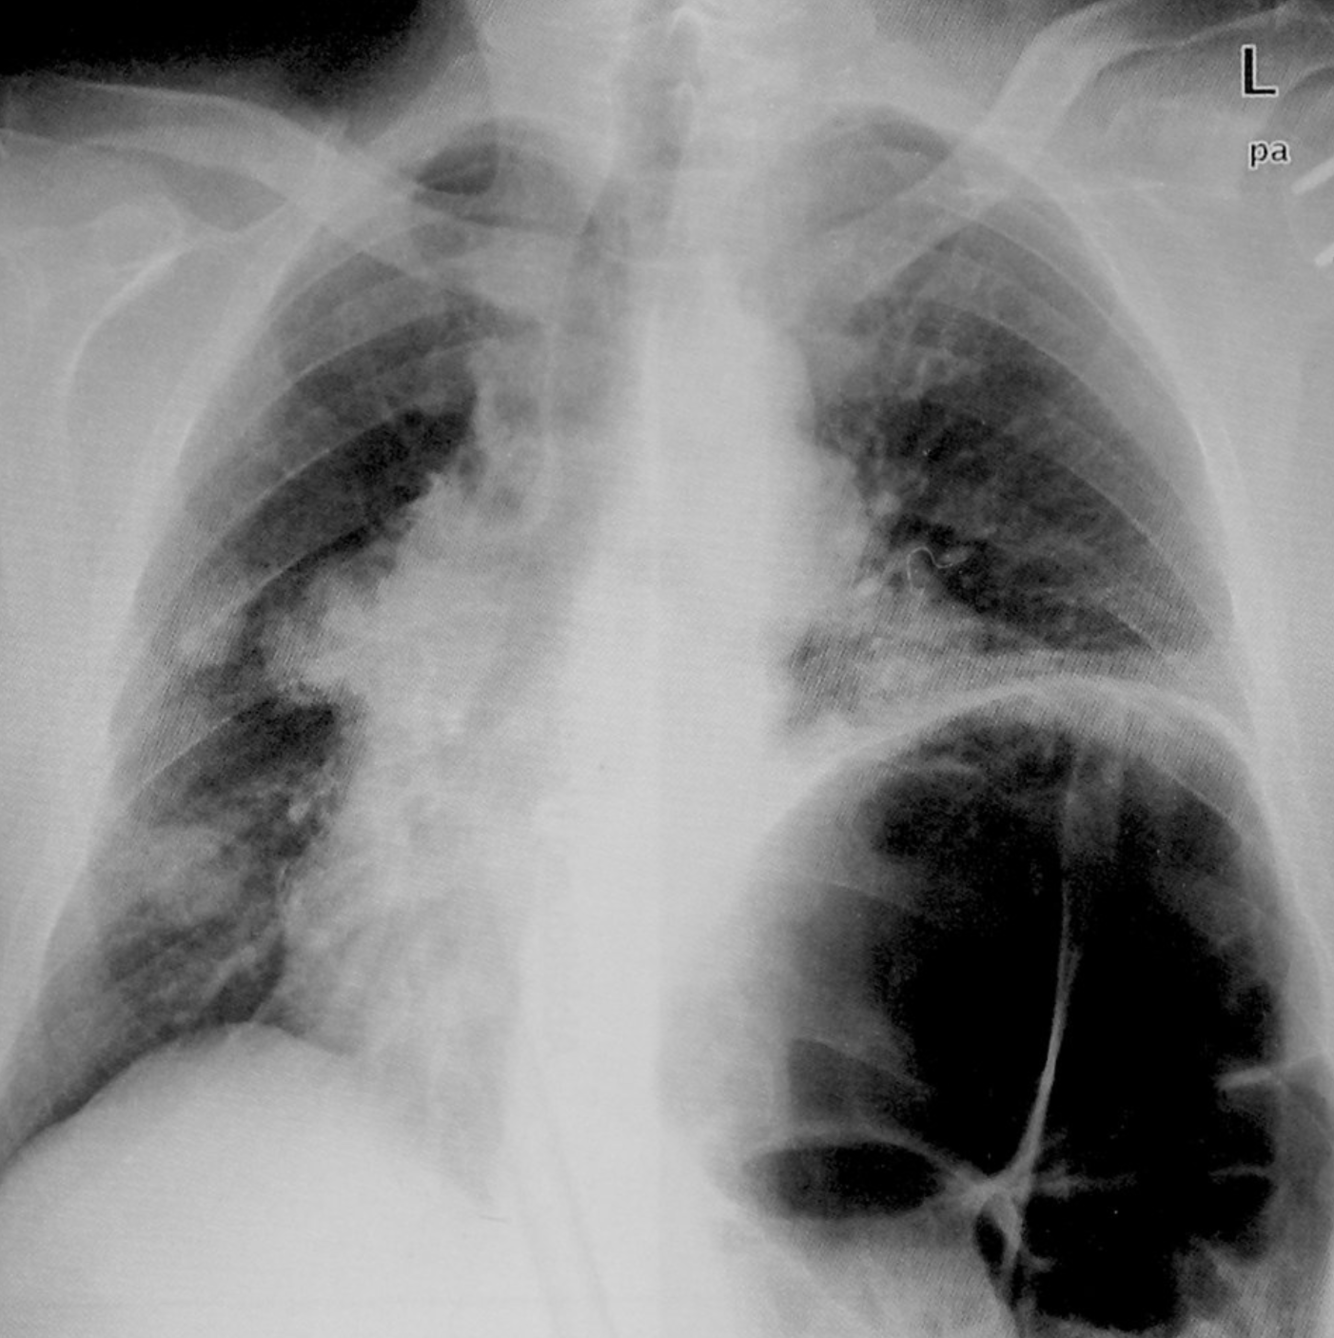

Post-primary tuberculosis

Posteroanterior chest x-ray showing bilateral apical, streaky parenchymal densities (green borders). These are most likely cavernous changes, which may occur during the course of post-primary tuberculosis. The full extent of cavernous formation can not be assessed on an x-ray; a CT scan should be performed.